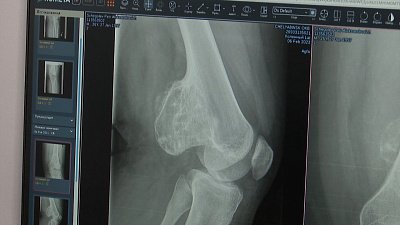

5-летний Владлен проходит лечение в детской областной клинической больнице. Сегодня его осматривают столичные врачи. Мама мальчика, Ольга рассказывает, что диагноз сыну пока не установили, но женщина уверена, что профессионалы смогут разобраться.

В составе выездной бригады РДКБ в Челябинск приехали — сосудистый хирург, гастроэнтеролог, уролог-андролог и пульмонолог. Столичные врачи рассматривают самые тяжелые случаи: где диагноз не ясен и требует уточнения схема лечения в рамках проекта «Территория здоровья» компании «НОВАТЭК».